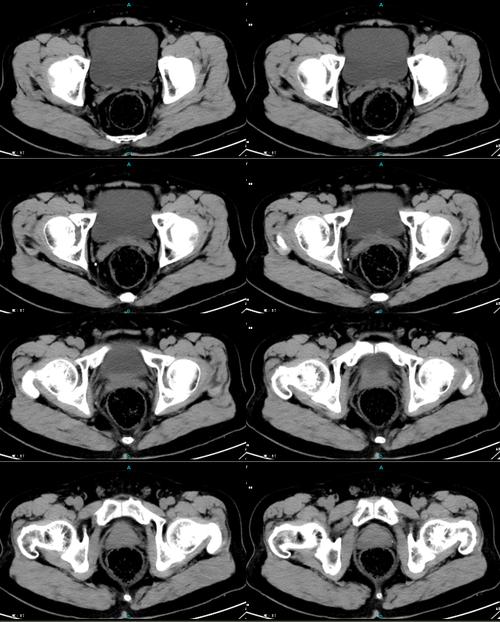

膀胱占位,膀胱位置

膀胱占位